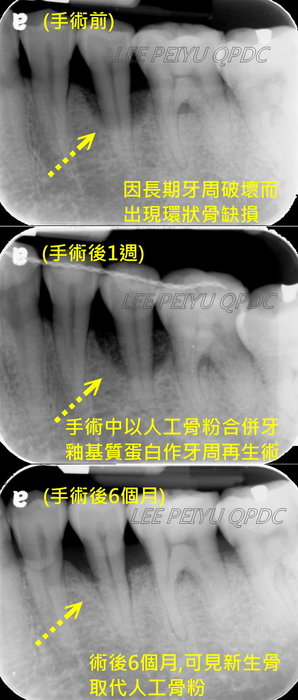

牙周治療

案例一